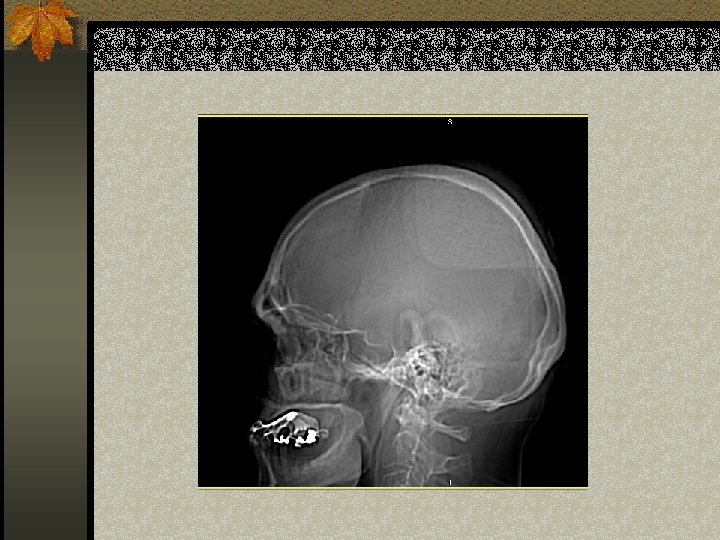

TEKNIK IMAGING n Adanya fraktur skull meningkatkan resiko adanya lesi intrakranial posttraumatic n Namun, ketiadaan fraktur skull tidak menyingkirkan suatu brain injury, dan hal ini terutama benar pada penderita anak-anak karena kapasitas skull untuk meregang n TIDAK ADA PERAN FOTO POLOS PADA TRAUMA KEPALA AKUT

PENDEKATAN PADA CT OTAK n Lihat pada scout film: adakah fraktur pada n n n upper cervical spine atau skull Lihat adakah asimetri otak Lihat pada sulci, Sylvian fissure dan cisterns untuk menyingkirkan perdarahan subarachnoid Ubah kondisi untuk menilai subdural collection Lihat pada kondisi tulang untuk fraktur Tentukan lesi tersebut intraaxial (di dalam otak) atau extraaxial (di luar otak)

SIGNIFICANT SKULL FRACTURES n “Depressed”: tabula interna tertekan melebihi ketebalan skull n Overlie major venous sinus, motor cortex, middle meningeal artery n Melewati sinus-sinus n Lihatlah sutural diastasis (lambdoid)